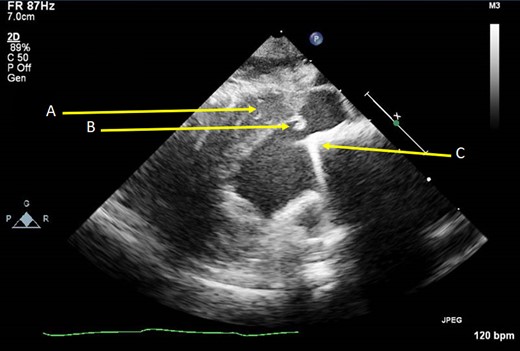

Examining the profile of each valve (Fig. 1), we believe the Carbomedics housing is more predisposed to cause obstruction than the St. Jude. The housing of the Carbomedics prosthesis extends more inferiorly than the St. Jude and potentially into the left ventricular cavity, impinging on the outflow tract. In a patient with coexisting septal hypertrophy, it is clear to see how these two factors alone could cause narrowing. As can be seen in the TTE slice in Fig. 2, the Carbomedics valve is protruding significantly into the LVOT. Severe LVOTO has previously been reported with a Carbomedics mitral valve which was subsequently relieved by replacing the prosthesis with a St. Jude valve [3].

Oblique parasternal long axis TTE image showing thickened IVS (A), subaortic fibrous material (B) and the protruding mitral valve prosthesis (C).

Thirdly, the fibrous band found encircling the LVOT (Fig. 2B) caused further restriction in flow. It is in our opinion that the band will likely have been formed due to turbulent flow from the valve protrusion, though repeated mitral valve prosthesis contact with the interventricular septum has also been shown to cause fibrous material development [4].